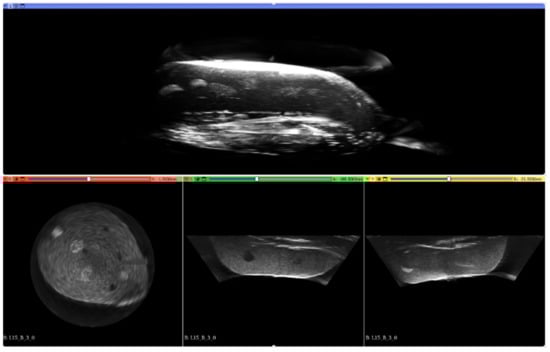

2.3. Imaging Geometry and Reconstruction

3. Results